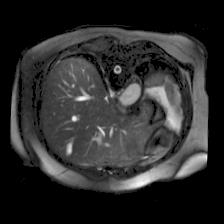

In clinical practice, well-aligned multi-modal images, such as Magnetic Resonance (MR) and Computed Tomography (CT), together can provide complementary information for image-guided therapies. Multi-modal image registration is essential for the accurate alignment of these multi-modal images. However, it remains a very challenging task due to complicated and unknown spatial correspondence between different modalities. In this paper, we propose a novel translation-based unsupervised deformable image registration approach to convert the multi-modal registration problem to a mono-modal one. Specifically, our approach incorporates a discriminator-free translation network to facilitate the training of the registration network and a patchwise contrastive loss to encourage the translation network to preserve object shapes. Furthermore, we propose to replace an adversarial loss, that is widely used in previous multi-modal image registration methods, with a pixel loss in order to integrate the output of translation into the target modality. This leads to an unsupervised method requiring no ground-truth deformation or pairs of aligned images for training. We evaluate four variants of our approach on the public Learn2Reg 2021 datasets \cite{hering2021learn2reg}. The experimental results demonstrate that the proposed architecture achieves state-of-the-art performance. Our code is available at https://github.com/heyblackC/DFMIR.